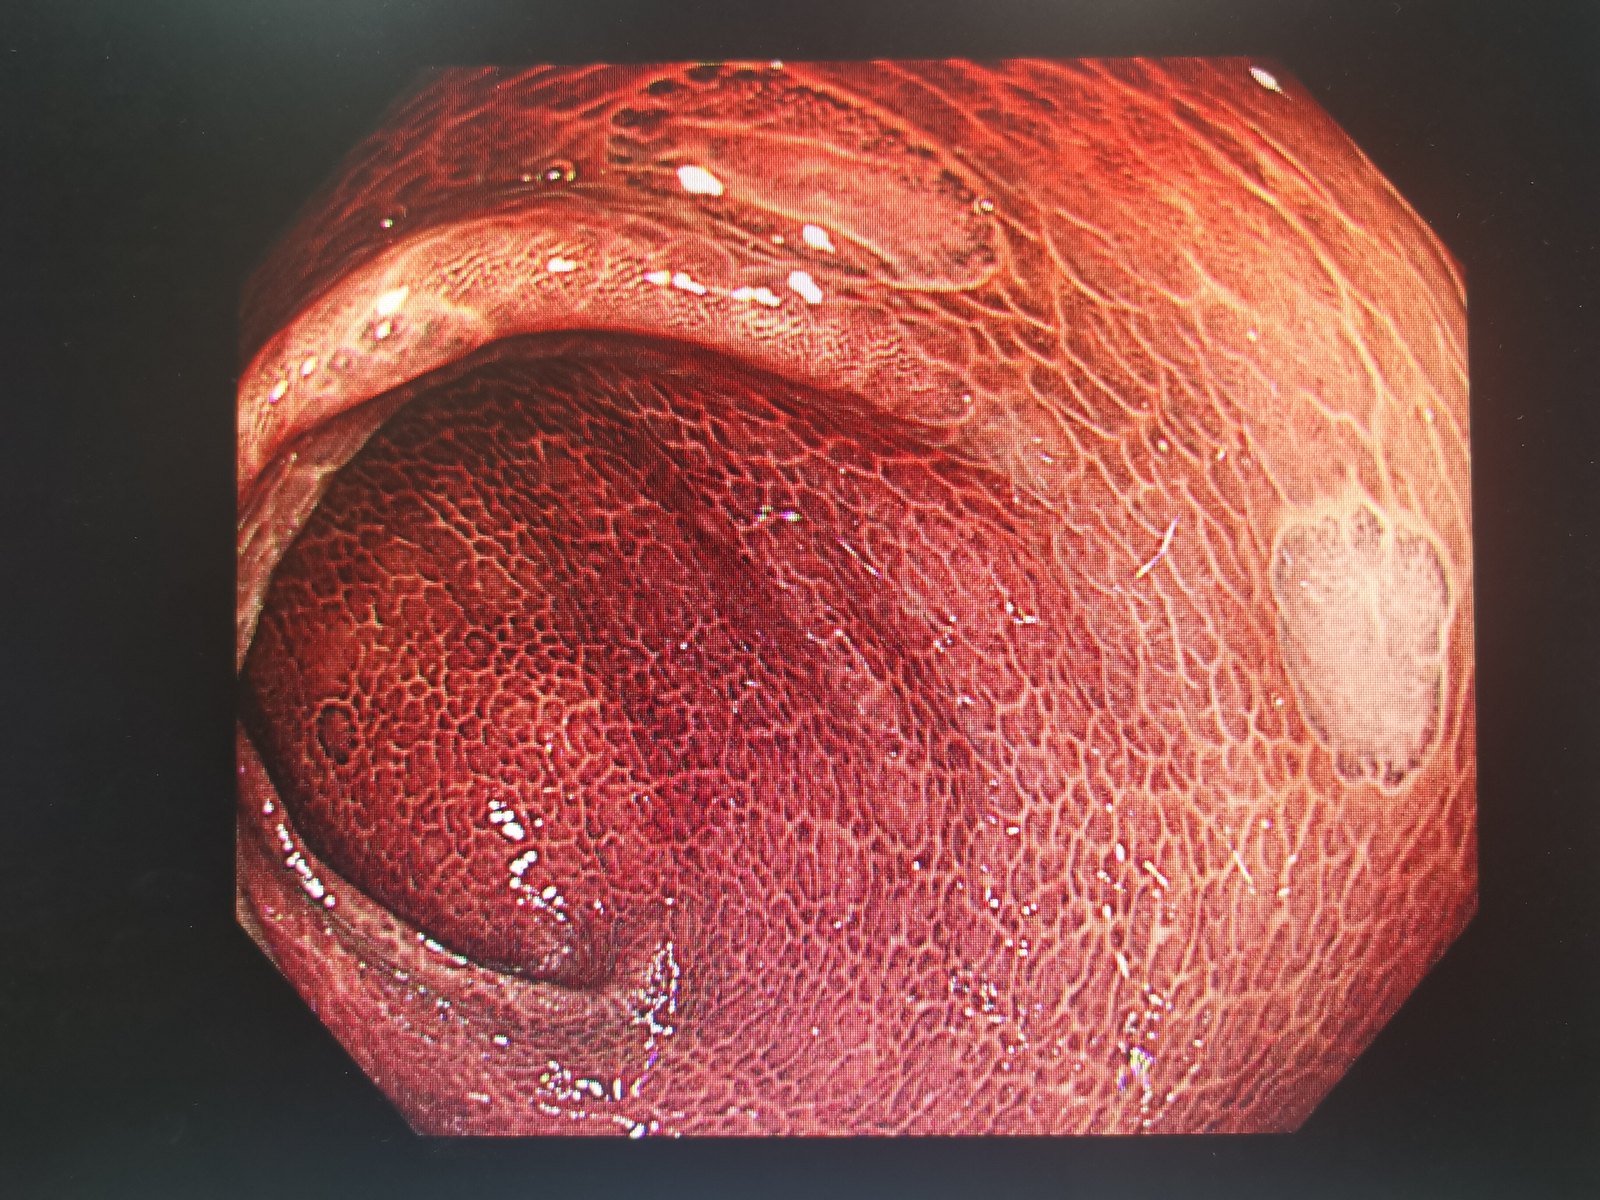

图片尺寸1600x1200

身体出现这几个症状该注意了|结肠炎|结肠|症状_新浪新闻

可怕的结肠黑变病_肠疾病_肠疾病相关疾病 - 好大夫在线

结肠黑变病下的sm2 ca.有点可惜,早点过来做检查说不定就 - 抖音

图片尺寸1195x1080